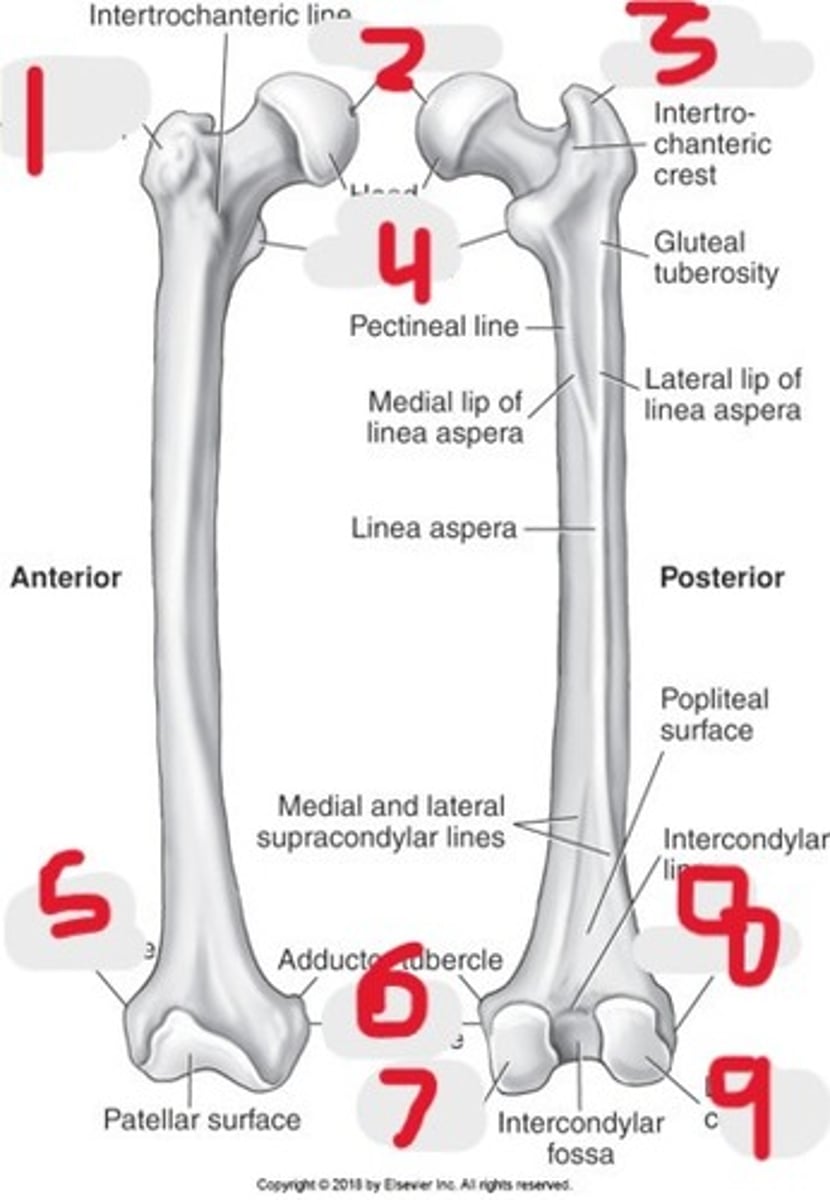

1) Greater trochanter

2) Fovea capitis

3) Greater trochanter

4) Lesser trochanter

5) Lateral epicondyle

6) Medial epicondyle

7) Medial condyle

8) Lateral epicondyle

9) Lateral condyle

Name all numbered structures